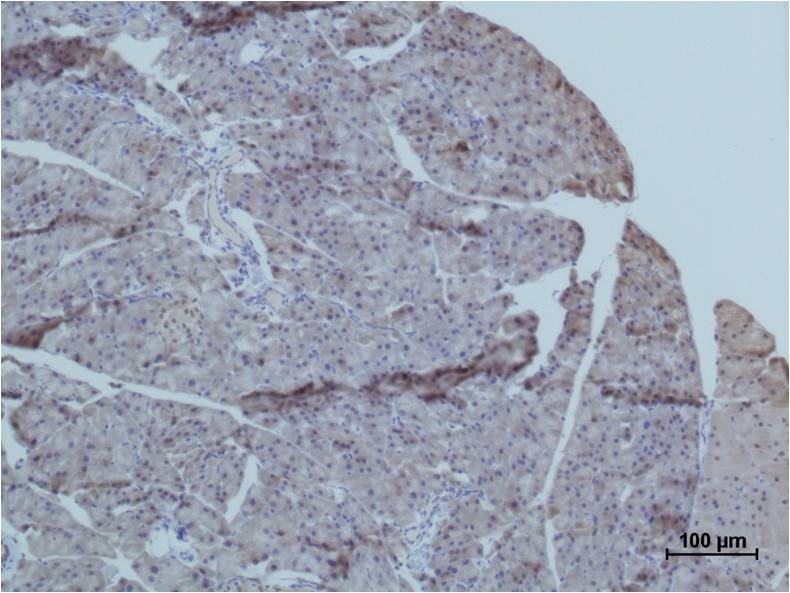

IHC 1/50-1/100 Human,Mouse,Rat

MG53 antibody is a research tool targeting the Mitsugumin 53 (MG53) protein, a muscle-enriched tripartite motif (TRIM) family protein primarily expressed in skeletal and cardiac muscle. MG53 plays a critical role in cell membrane repair by forming repair complexes that traffic to sites of membrane injury. It also exhibits E3 ubiquitin ligase activity, influencing proteasomal degradation and cellular homeostasis. Studies highlight its involvement in metabolic regulation, inflammatory responses, and tissue protection, linking it to conditions like diabetes, muscular dystrophy, and ischemia-reperfusion injury. Researchers use MG53 antibodies in Western blotting, immunohistochemistry, and functional assays to study its expression, localization, and mechanistic roles in disease models. While preclinical studies suggest therapeutic potential for MG53 in enhancing tissue repair or mitigating metabolic disorders, debates persist regarding its dual roles. For example, elevated MG53 levels in diabetes may contribute to insulin resistance, complicating its therapeutic targeting. The antibody thus serves as a vital reagent for elucidating MG53's pathophysiological functions and evaluating its candidacy for clinical translation. Ongoing research aims to resolve controversies and explore its modulation in regenerative medicine and chronic diseases.